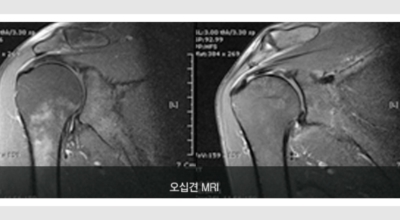

오늘 살펴 볼 것은 오십견 증상에 대한 내용인데요 이유 없이 어깨가 뻐끈하고 아픈 분들 계시죠. 이럴때는 흔히 들어본 오십견인가 걱정하기 마련인데요 오십견에 대한 정확한 정보를 확인해 보시고 진찰 받아보시기 바랍니다.

오십견이란 어깨의 통증과 어깨관절의 운동범위 제한을 특징으로 하는 질환으로 특히 50대 이후에 많이 발생함으로 오십견이라 이름이 지어졌으며 어깨관절이 얼어붙었다는 뜻으로 동결견(frozen shoulder)이라고도 합니다. 어깨관절의 운동성이 소실되기 때문에 옷 입기, 머리 감기, 물건 들기 등의 일상생활에 많은 어려움이 유발되며 통증으로 인해 잠을 못자는 경우도 대부분이 발생하게 되어요.